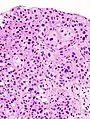

| Histopathology of transitional carcinoma of the urinary bladder. Transurethral biopsy. Hematoxylin and eosin stain. | |

Histopathology of urothelial carcinoma of the urinary bladder.